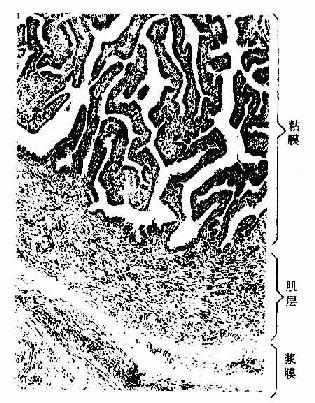

图17-10 人输卵管壶腹部 HE × 83

输卵管主要分漏斗部、壶腹部、峡部和子宫部,管壁均由粘膜、肌层和浆膜三层组成。

粘膜形成许多纵行而分支的皱襞,壶腹部的皱襞最发达,高而多分支,故管腔不规则(图17-10);至子宫部的皱襞渐减少。粘膜上皮为单层柱状。由纤毛细胞和分泌细胞组成(图17-11)。纤毛细胞以漏斗部和壶腹部最多,至峡部和子宫部逐渐减少,纤毛向子宫方向摆动,使卵移向子宫并阻止病菌进入腹膜腔.分泌细胞表面有微绒毛,顶部胞质内有分泌颗粒,其分泌物构成输卵管液。输卵管上皮细胞在卵巢雌激素和孕激素的作用下,随月经周期而有变化。雌激素促进输卵管上皮细胞的生长的功能活动,在子宫内膜增生晚期(排卵前)。纤毛细胞变成高柱状,纤毛增多,分泌细胞顶部充满分泌颗粒,功能旺盛。至分泌晚期,两种细胞均变矮,分泌细胞的分泌颗粒排空,纤毛细胞的纤毛也减少。在月经期和妊娠期,上皮细胞矮小。粘膜固有层为薄层细密的结缔组织,并有少量散在的平滑肌。

肌层以峡部最厚,由内环行和外纵行两层平滑肌组成。壶腹部肌层较薄,环行肌明显,纵行肌散在分布。输卵管浆膜由间皮和富含血管的疏松结缔组织组成。